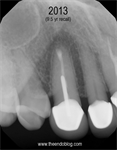

9.5 year recall.  Tooth is fully functional, asymptomatic with radiographic healing.  Apicoectomy has preserved the tooth and the periodontium for an extended period of time.